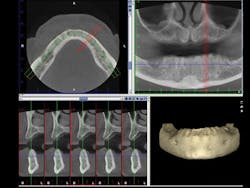

Figure 3: An example cone beam image shows in the upper right image the typical 2-D view of the maxilla and mandible. The lower left image shows the maxilla and mandible view 90 degrees from the upper right image. Planning for implant placement is greatly improved by cone beam images.